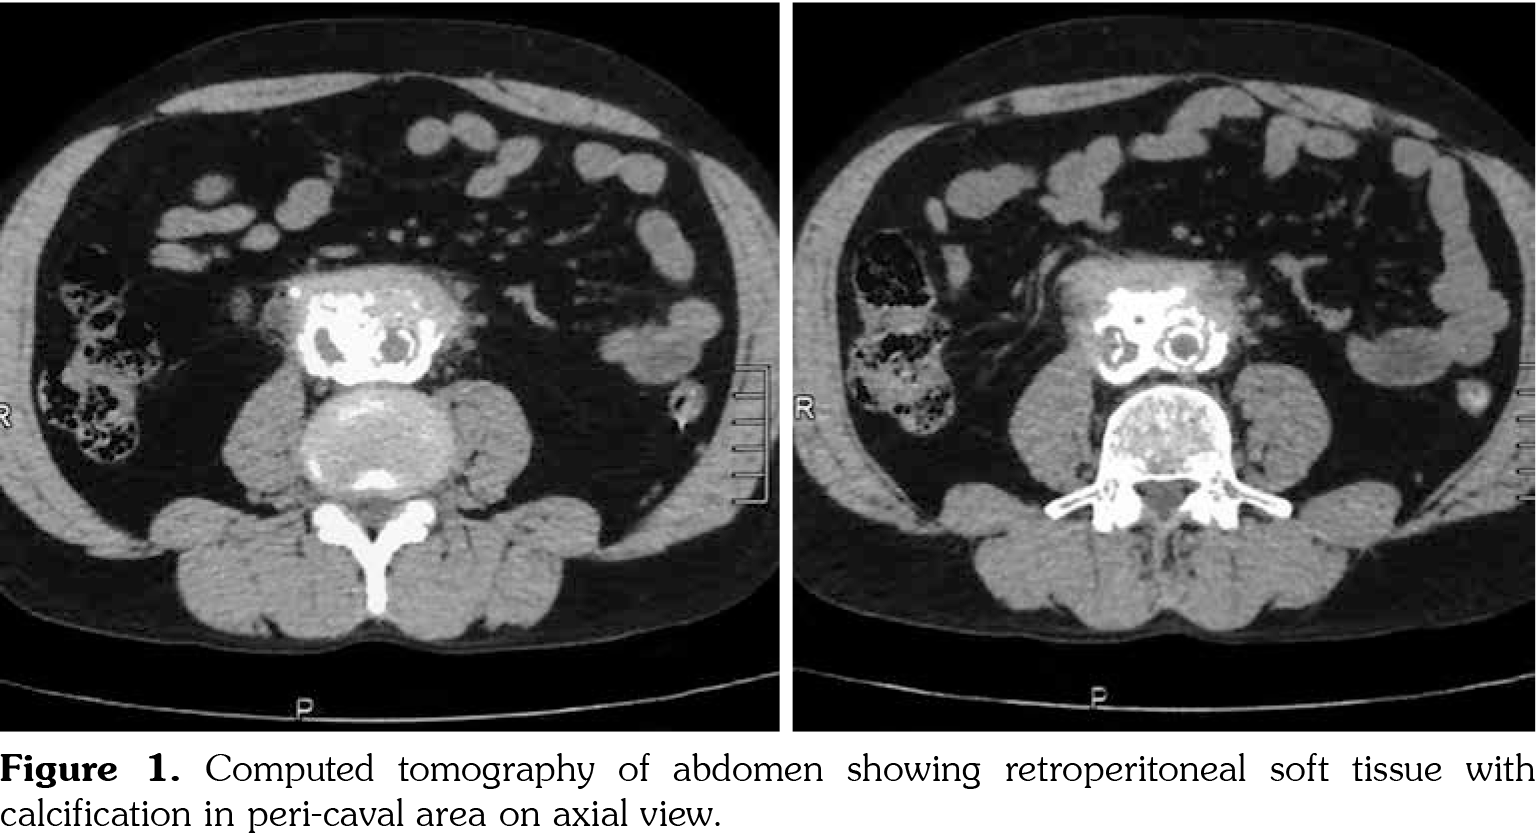

On investigations, his complete blood count was normal. Erythrocyte sedimentation rate was 88 mm in first hour. Random blood sugar was 93 mg/dL. His serum urea was 26 mg/dL and serum creatinine was 1.1 mg/dL. Liver function tests were within normal limits. Chest X-ray revealed non-homogenous opacities in bilateral lung fields. Pulmonary function tests revealed forced expiratory volume in one second (FEV1) of 61% and forced vital capacity (FVC) of 73%. FEV1/FVC ratio was 84%. Two-dimensional echocardiography was within normal limits. Ultrasonography of the abdomen revealed small-sized right kidney (6.9x2.9 cm) with dilated pelvi-calyceal system and dilated proximal ureter. Computed tomography (CT) of the abdomen revealed medial deviation of right ureter and presence of retroperitoneal soft tissue along infra-renal aorta and peri-caval area with calcification extending up to iliac vessels suggestive of RPF (Figures 1, 2, 3, and 4). High-resolution CT of the chest confirmed presence of interstitial lung disease (ILD). ANA profile (ENA) revealed that anti-U1 snRNP was strongly positive. Rest of the autoantibodies were negative. His serum immunoglobulin G levels were within normal limits. Thus, we arrived at a diagnosis of MCTD with RPF and ILD. He was started on mycophenolate 720 mg twice daily, hydroxychloroquine 200 mg once daily and deflazacort 6 mg once daily for MCTD, pirfenidone 400 mg twice daily for ILD and tamoxifen 20 mg once daily for RPF. On follow-up at six months, he was doing physically well. His symptoms of cough were reduced and dyspnea improved from NYHA class IV to class II. Repeat pulmonary function tests revealed FEV1 of 59%, FVC of 71% and FEV1/FVC ratio of 84%. However, repeat ultrasonography of the abdomen did not reveal any significant change in pelvi- calyceal system.